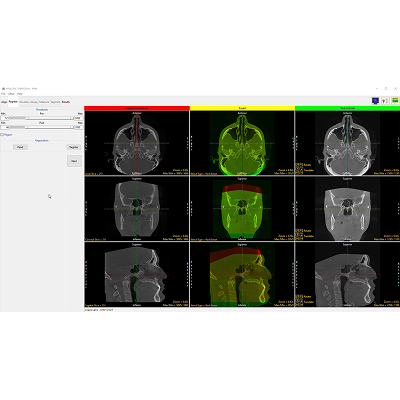

Segmentation Comparison

Selecting the Segmentation Comparison action button will display a selection of renderings generated from the two object maps that have been defined for the Pre and Post volumes. The Renderings section provides checkboxes to choose which comparison renderings to display.